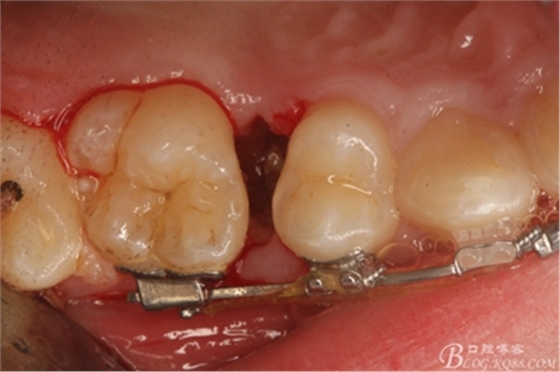

圖8.因16與14合面的間隙僅2mm左右,牙根無法合向脫位,如何考慮15牙根的脫位將是最大問題。高速手機去除牙間隙內(nèi)的覆蓋在15牙根表面的牙齦組織

圖10.去除牙齦組織后。露出15牙根斷面,合面無法脫位